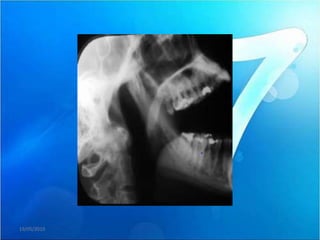

b) BLOQUEO ABIERTO O LUXACION

 Situación clínica en la que el cóndilo está

posicionado por delante de la eminencia

articular y no es capaz de volver a su posición

inicial (boca cerrada) debido al espasmo de la

musculatura masticatoria.

•    Imposibilidad de cerrar la boca.

•     Depresión preauricular de la piel.

•    Aumento de la salivación.

•    Espasmo de los músculos masticatorios.

•    Dolor severo a nivel de la articulación

témporo-mandibular (ATM).